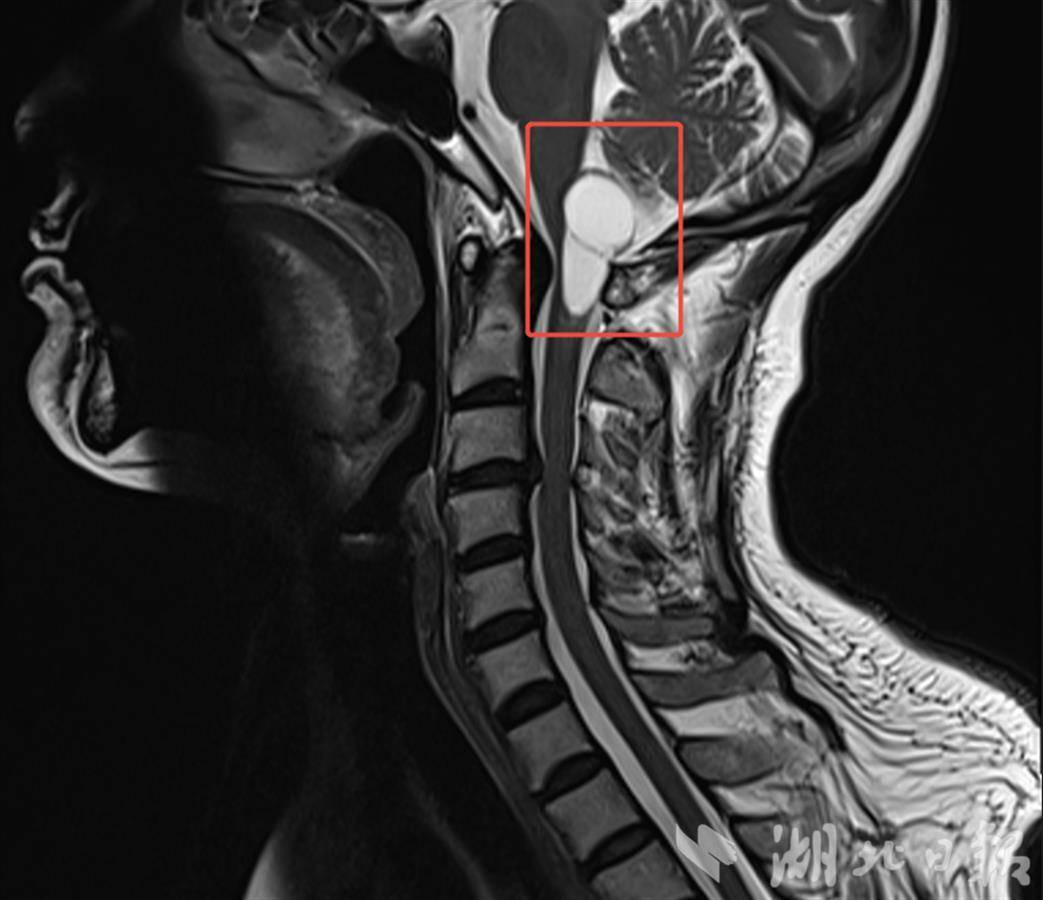

2月3日,62岁的陈女士(化姓)因进行性加重的肢体麻木来到泰康同济就诊,经影像学检查确诊为“脑干-延髓及颈髓交界区占位性病变”。该区域密布呼吸、心跳中枢及重要神经传导束,手术中稍有不慎,就可能导致呼吸心跳骤停、永久性瘫痪,甚至死亡的严重后果,被医学界公认为“手术禁区”。

“脑干手术是对技术与勇气的双重考验。”泰康医疗神经医学中心首席专家陈劲草教授说。经过详细的术前评估和多学科专家讨论,神经外科团队制定了一套精准且个性化的手术方案。2月8日,手术如期开展,通过枕下后正中入路实施显微镜下精细操作,术中对肿瘤边界进行了毫米级剥离,完整切除了病变组织,同时完美避开脑干核团及神经传导束。